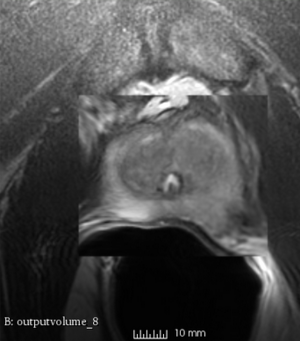

We used this sample data with Reader 1 segmentations to visually evaluate differences in the registration results. All three results of BRAINSFit with ITKv3 in Slicer 3.6 look reasonable. Using BRAINSFit with ITKv4 in Slicer 4.4 creates a reasonable result for Case 7, but look strongly distorted towards the edges of the bounding box in Case 8 and 9.

Case 7

Reference intraop volume

Reg Result Slicer 3.6 with ITKv3

Reg Result Slicer 4.4 with ITKv4